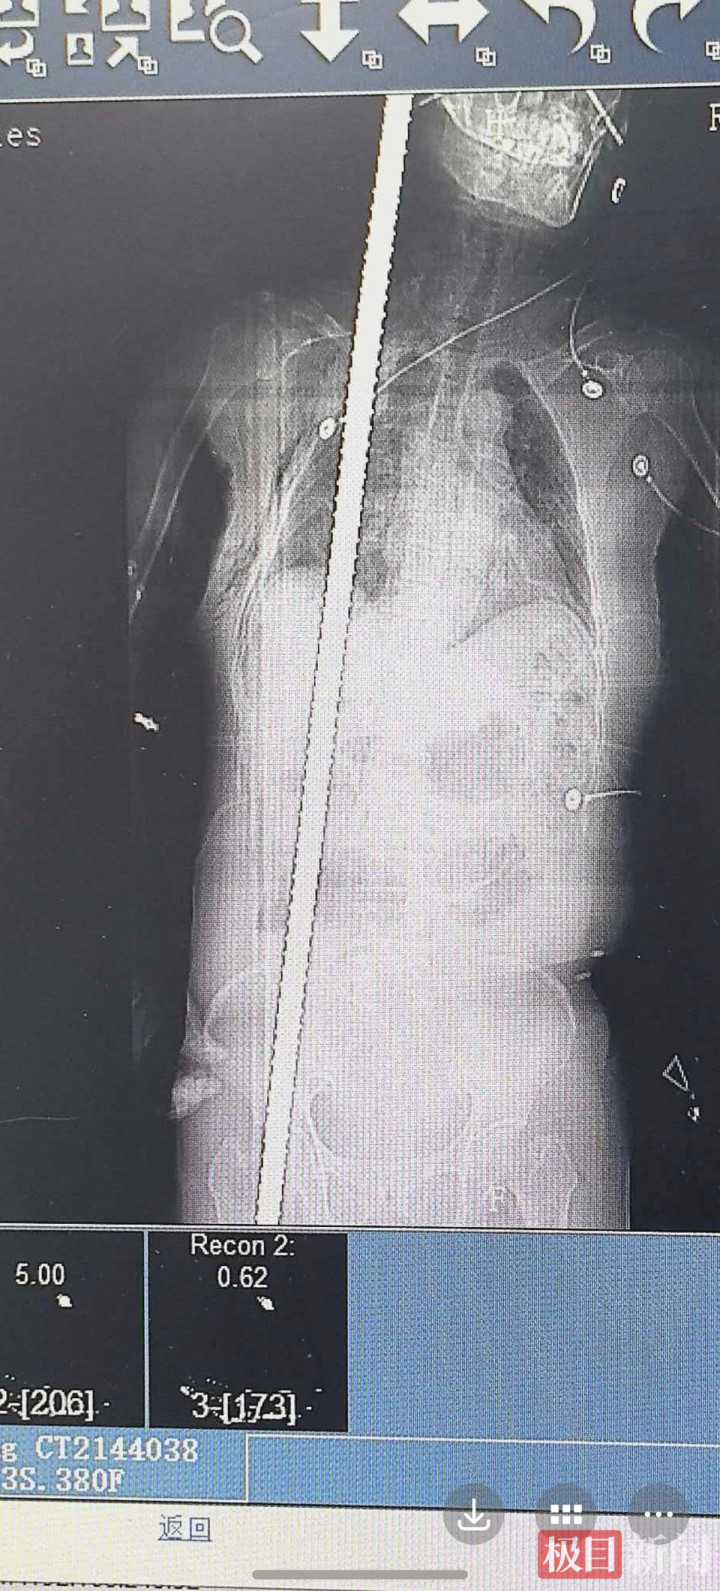

1月10日,张女士在手术前进行了影像学检查

紧急CT结果印证了最坏的担忧:钢筋在体内贯穿出一条极度凶险的“隧道”,它紧贴右侧锁骨下动静脉(人体上肢主要供血血管)、完全穿透右肺、刺破膈肌、紧邻肝门区(肝脏血流总枢纽)、损毁右肾、造成骨盆骨折,末端从大腿根部穿出。任何一处大血管破裂,或引发严重感染,都足以致命。